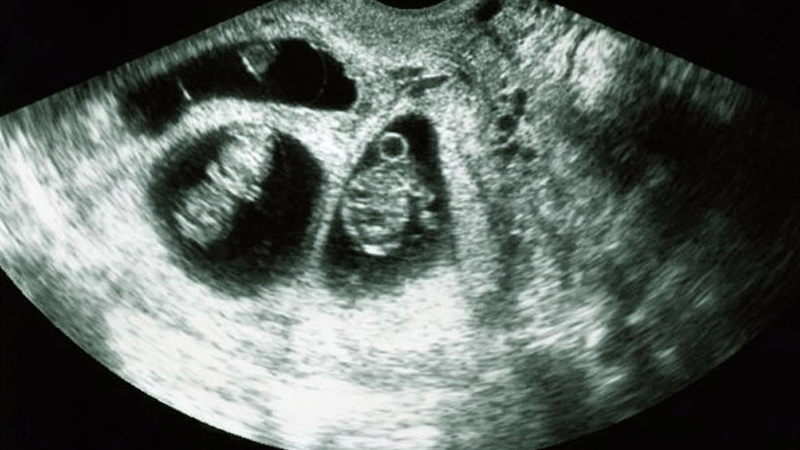

ربط البروفيسور أناتولي إيشينكو رئيس قسم أمراض النساء والتوليد بجامعة سيتشينوف الطبية، صحة الجنين بعمر الوالدين.

وقال البروفيسور في حديث لصحيفة “إزفيستيا”: “يبلغ متوسط عمر المرأة عند ولادة طفل في الوقت الحاضر ما يقرب من 29 عاما. أما في القرن الماضي، وخاصة في بدايته، كانت المرأة تحمل بأول طفل في عمر 19 عاما. كانت النساء في ذلك الوقت يلدن مبكرا وكثيرا، أما الآن فقد تغير كل شيء”، وذلك كما ذكرت صحيفة “روسيا اليوم”.

ويقول: “أما في الوقت الحاضر، يعمل الشخص قبل كل شيء على تكوين نفسه ومن ثم يتزوج وبعد أن يبني مستقبله، يفكر بإنجاب طفل. أي بعد أن يكون قد تقدم بالعمر. وهذا للأسف الشديد يؤدي إلى ارتفاع خطر ولادة أطفال مرضى. مشيرا إلى أن هذا الخطر يزداد بصورة خاصة بعد سن الـ 35 عاما وبصورة حادة بعد الـ 40 عاما”.